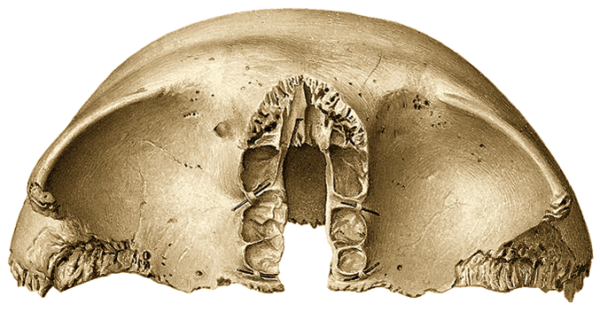

- Cavidades de recepción: Su función principal es alojar y proteger estructuras blandas, como tendones, vasos sanguíneos y nervios. Su morfología es diversa e incluye canales, surcos, incisuras y conductos que guían estas estructuras y las resguardan frente a traumatismos. Ejemplos de gran relevancia incluyen las fosas craneales, que contienen y protegen el encéfalo, y la fosa hipofisaria, que aloja la hipófisis. Estas cavidades permiten, además, un ordenamiento espacial eficiente dentro del esqueleto, evitando interferencias entre tejidos y optimizando la funcionalidad.